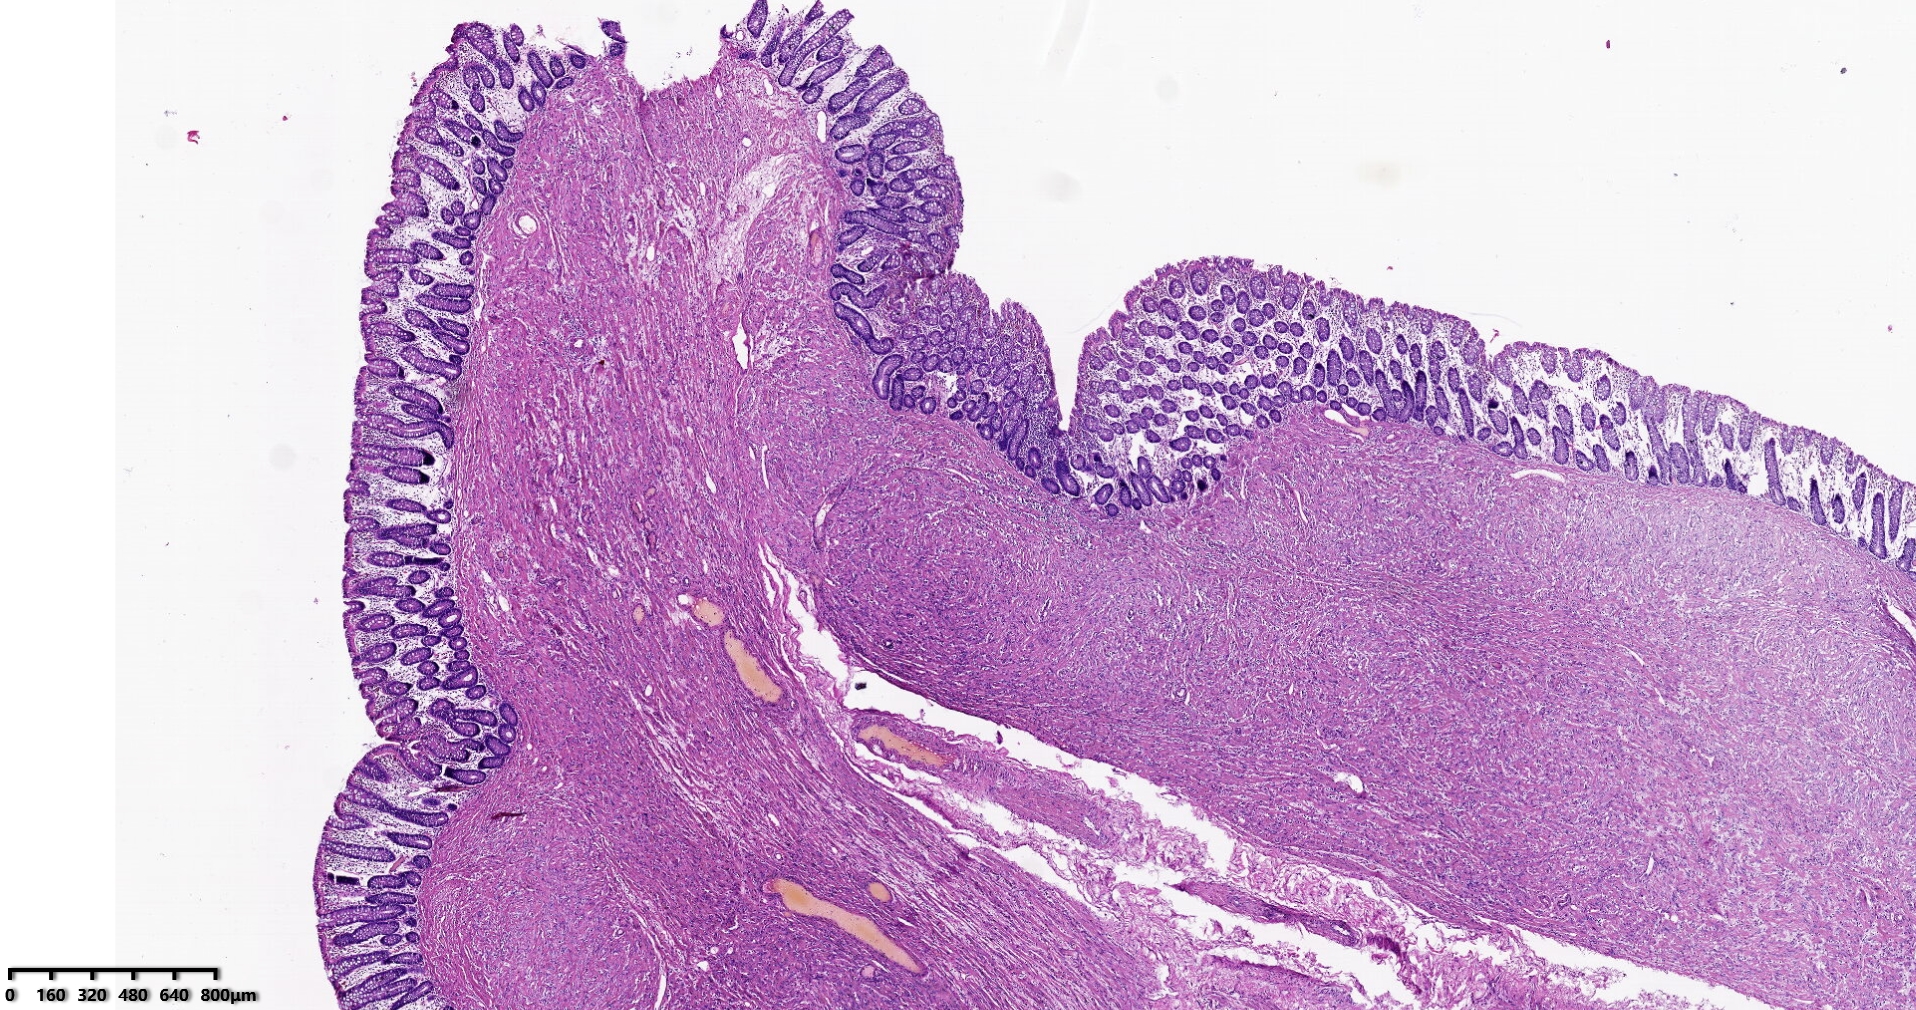

结肠肝曲息肉状肿物,平滑肌瘤?胃肠道间质瘤?炎性纤维性息肉?

性别

男

年龄

56岁

临床诊断

结肠肝曲息肉

一般病史

不详

标本名称

大体所见

灰红色椭圆形息肉一个,直径2.5cm,蒂长0.5cm,切面灰白灰红色,质中。

请路过的老师指教。

考虑间质瘤?

就HE形态而言,间质瘤的可能性要大一些,建议做免疫组化协助鉴别。